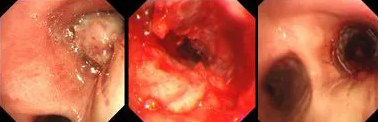

氣短、胸悶、呼吸困難,80歲的患者秦爺爺已經(jīng)出現(xiàn)了瀕死癥狀;局麻、右主支氣管再通,僅用6秒,胸科專家順利實施TTS氣道支架手術。

原來,秦爺爺入院時診斷為“右主支氣管”鱗狀細胞癌伴壞死。他的右主支氣管被腫瘤完全堵塞,混合性狹窄。面罩吸氧10升/分的狀況下,指脈氧只有85%,無法平躺,呼吸困難,病情十分危急,隨時有生命危險。

經(jīng)評估并與家屬溝通同意后,歐陽海峰副院長決定為患者實施TTS氣道支架手術。手術當天,在麻醉手術中心的配合下,歐陽海峰副院長為患者在局麻下快速凍切腫瘤組織,實現(xiàn)右主支氣管再通,并經(jīng)氣管鏡活檢孔道迅速植入14*30 TTS支架一枚。支架植入過程耗時僅6秒,迅速緩解了患者的氣短瀕死癥狀。